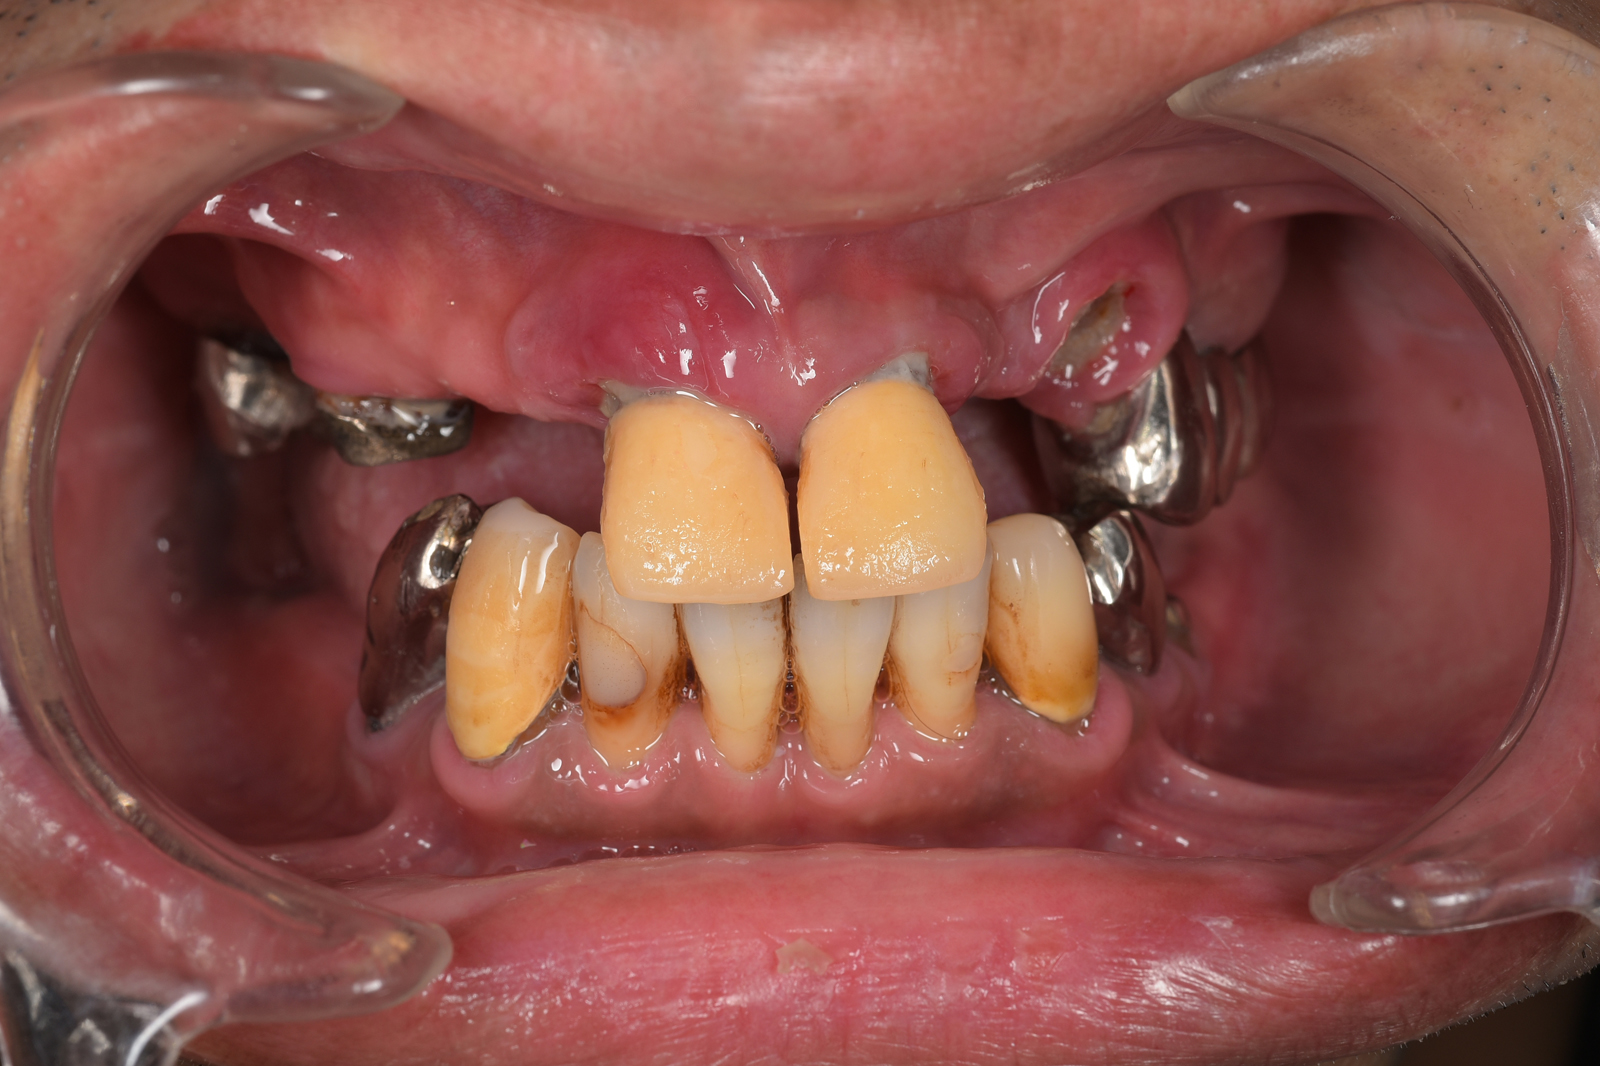

皆さんもご存じかと思いますが、歯周病は、歯を支える骨をゆっくり溶かしていき、痛くもないのに歯が抜けていくという恐ろしい病気です。

歯周病で歯が抜けてしまうのは、骨を支えている骨が溶けてしまうからです。骨を再生できれば、歯を残せる可能性が高まります。当院では、「エムドゲイン」という薬品を使って、骨の再生に取り組みます。

※症例によっては適応できず抜歯を避けられないこともあります。

エムドゲインは、特殊なたんぱく質を含む薬品です。患部を切開し、骨が失われた部分にエムドゲインを入れると、骨の再生が促進されます。個人差はありますが、数ヶ月〜1年程度で骨が再生されます。

病状が進んで歯周ポケットが深くなってくると、治療器具が届かなくなり、通常の方法では歯石を取り除けなくなります。このような場合、外科的に歯肉を切開して歯石を取り除く「歯周外科治療」を行います。

歯肉を切り開いて、奥深くの歯石を取り除く治療法です。直接目で見ながら歯石を取り除くので、取り残しがほとんどありません。

奥歯の根はいくつかに分かれています。歯周病が進行して奥歯を支える骨が溶けてくると、歯の根の分かれ目が露出してしまいます。ここに歯石が付着すると、通常の方法では取り除けません。放置していると歯周病は進行し、やがて抜歯になってしまうでしょう。

こういった症例に効果的な治療法が、ルートセパレーションです。歯を2〜3に分割して掃除しやすくした上で、かぶせ物を装着して見た目や機能を回復させます。